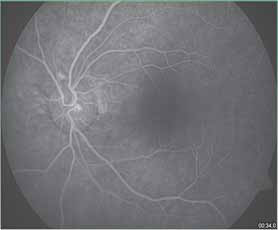

duration. The patient also had cerebral infarction. The vision ��� ���� ��������� ���� ���� ������ ��������� ������ ��� ������ ������������ ��� ���� ����������� ���� ������� ������ ���� ����� ������������� �������������� �������� ���� ������������ ������������showed pruning of the macular vessels in the perifoveal region. (Figure 3b)